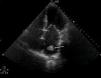

After reperfusion, signs of hypoperfusion persisted in the patient's lower limbs. In view of this finding, together with difficulty in femoral access, aortography was performed, which revealed thrombotic occlusion of the infrarenal abdominal aorta, extending to the iliac arteries (Figure 3). The echocardiogram showed a mass in the left atrium, consistent with a thrombus (Figure 4). Thromboembolectomy of the left iliac axis and femoro-femoral bypass were performed, but the patient developed multiple organ failure and died.